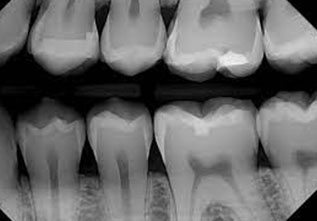

BITEWING RADIOGRAPHS

Bitewing radiographs are indicated primarily to detect or monitor hidden caries in the interdental tooth surfaces. Very useful for a dentist, as the proximal surfaces of the teeth cannot be visually examined or clinically accessible with dental explorers.